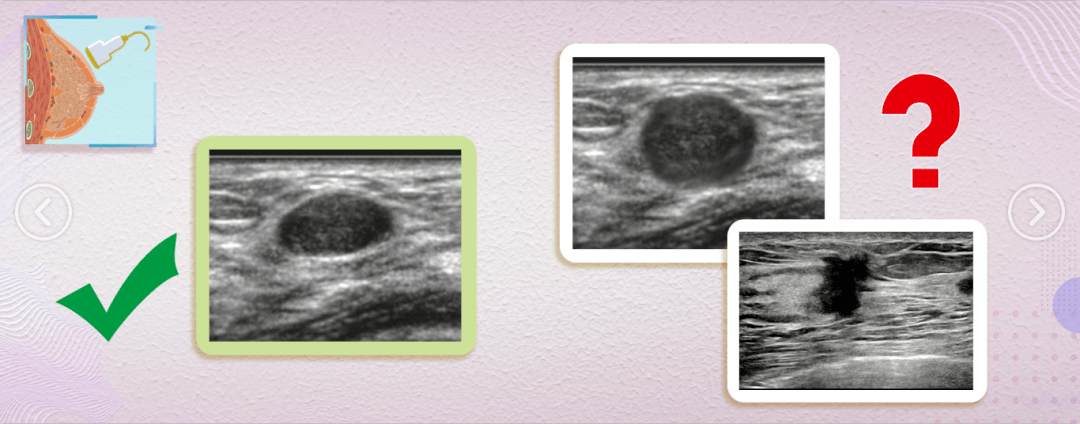

①形状不规则、边界不清楚

如果是良性的,往往形状规则,会轻轻推挤周围的腺体,形成光滑的边界;

如果是恶性的,通常形状不规则,而且会侵犯到周围组织,导致边界不清。

②纵横比>1

若纵小于横,肿瘤是趴着长的,往往是良性的;

若纵大于横,即纵横比>1,肿瘤是立着长的,更倾向于恶性。